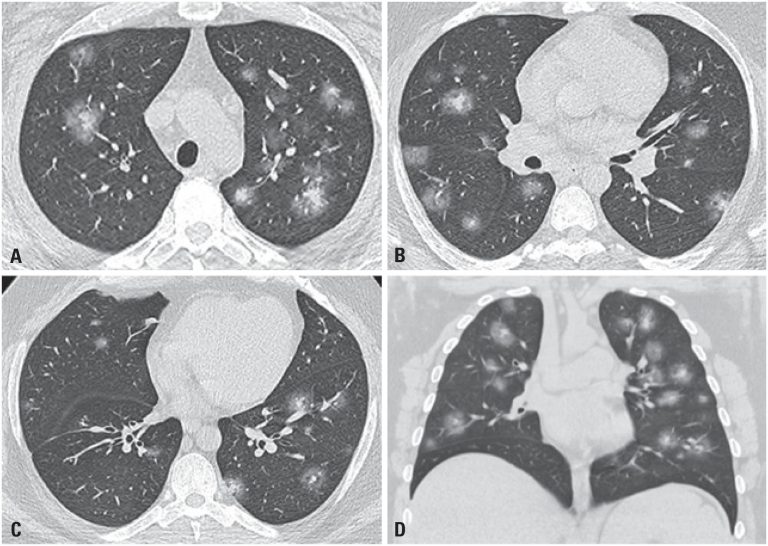

Paciente do sexo masculino, 36 anos de idade, natural e procedente de Nova Jersey (Estados Unidos), obeso, hipertenso e diabético, compareceu ao nosso serviço sudoreico, taquipneico, taquicárdico e febril (38,6°C) e saturando 90% em ar ambiente. Relatou que, há 5 dias, procurara um serviço médico nos Estados Unidos por queixa de tosse seca, coriza, mal-estar e febre referida. Na admissão, o paciente realizou radiografia () e tomografia computadorizada () de tórax, que evidenciaram múltiplas pequenas opacidades nodulares e consolidações esparsas por ambos os pulmões, com distribuição periférica e central, acompanhadas de halo em vidro fosco, configurando o sinal do halo. A pesquisa da infecção por coronavírus por meio de reação em cadeia da polimerase com transcrição reversa (RT-PCR) detectou a presença do RNA do vírus no material colhido da nasofaringe do paciente.

Os achados tomográficos da pneumonia na doença pelo novo coronavírus tipo 2 (SARS-CoV-2), a coronavirus disease 2019 (COVID-19), são inespecíficos e podem ser encontrados em outras etiologias virais e nas pneumonias em organização. O aspecto mais comum inclui opacidades em vidro fosco pulmonares multifocais, associadas ou não às áreas de consolidação ou espessamento septal (configurando aspecto de “pavimentação em mosaico”), apresentando distribuição bilateral, principalmente nas regiões pulmonares periféricas.() A tomografia computadorizada pode ser usada nos pacientes sintomáticos, inclusive com relato de maior sensibilidade, mas especificidade limitada em relação ao teste molecular padrão,(,) porém não é recomendada para o rastreio pela maioria das sociedades.()